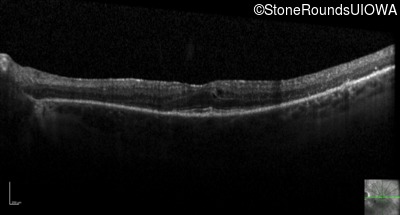

Optical Coherence Tomography - Right - 20/50 +1

Exemplar / OCT Stack